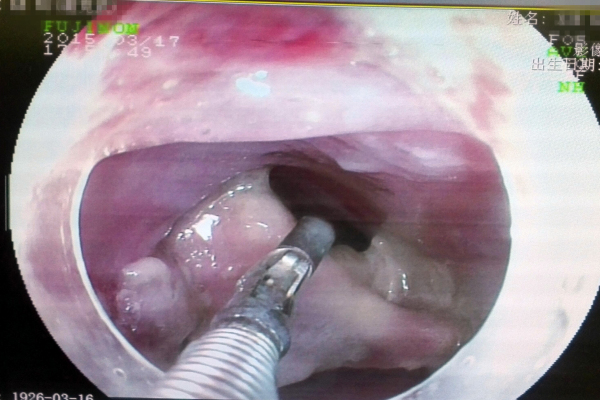

由于手术难度高,风险大,整个病房的医生们也都来了,紧张的手术室里,消化内镜中心的袁海锋主任、黄金锐护士长等人正有条不紊严密配合着,虽然提心吊胆,但每个手术步骤都要做到精准控制,在旁边的医生也都捏了一把汗,“在主刀医生成功取出约3cm*4cm异物(骨头)的时候,手术室里二十几个人不约而同鼓起掌,大家长长地松了一口气”。

内镜下异物取出手术